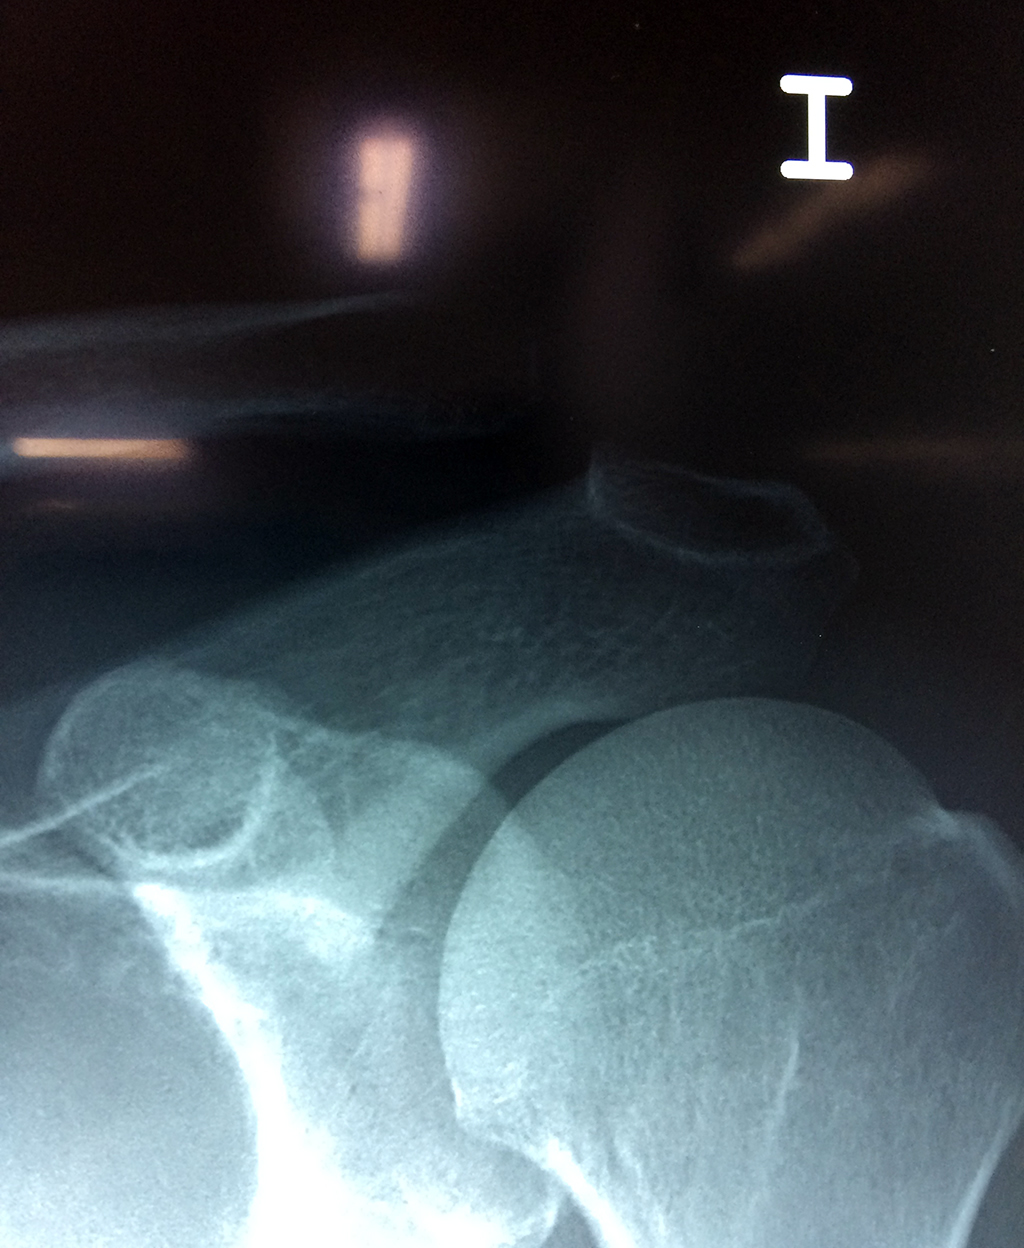

Cirugías de Codo - Clavícula

La clavícula es un hueso largo, con forma de "S" itálica, situado en la parte anterosuperior del tórax. Junto con la escápula forman la cintura escapular. Se puede palpar por toda su longitud y se extiende del esternón al acromion de la escápula, siguiendo una dirección oblicua lateral y posterior.